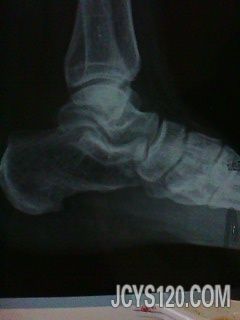

• 脚跟痛 attach_img agree

• wjl8742693 2013-1-19

• 右脚跟疼痛伴肿胀5天。 患者女性,工人,五天前患者突然感脚跟不能落地行走,伴肿胀,压之疼痛感明显,无其他不适。 瞩患者行X线检查。服药骨刺胶囊,效果甚微。 X线片示:寻求良方。谢谢啦。  阅读全文>